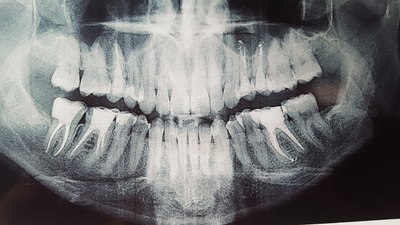

Через месяц протезированный 47й зуб заболел заболел и я обратилась в клинику номер 2. Мне сделали снимок 47го зуба, который показал воспалительный процесс в области верхушек корней. Дабы исключить сомнения, я съездила и сделала компьютерную томографию 47го зуба. КТ показала воспаление не только в области верхушек, но и между корнями зуба.